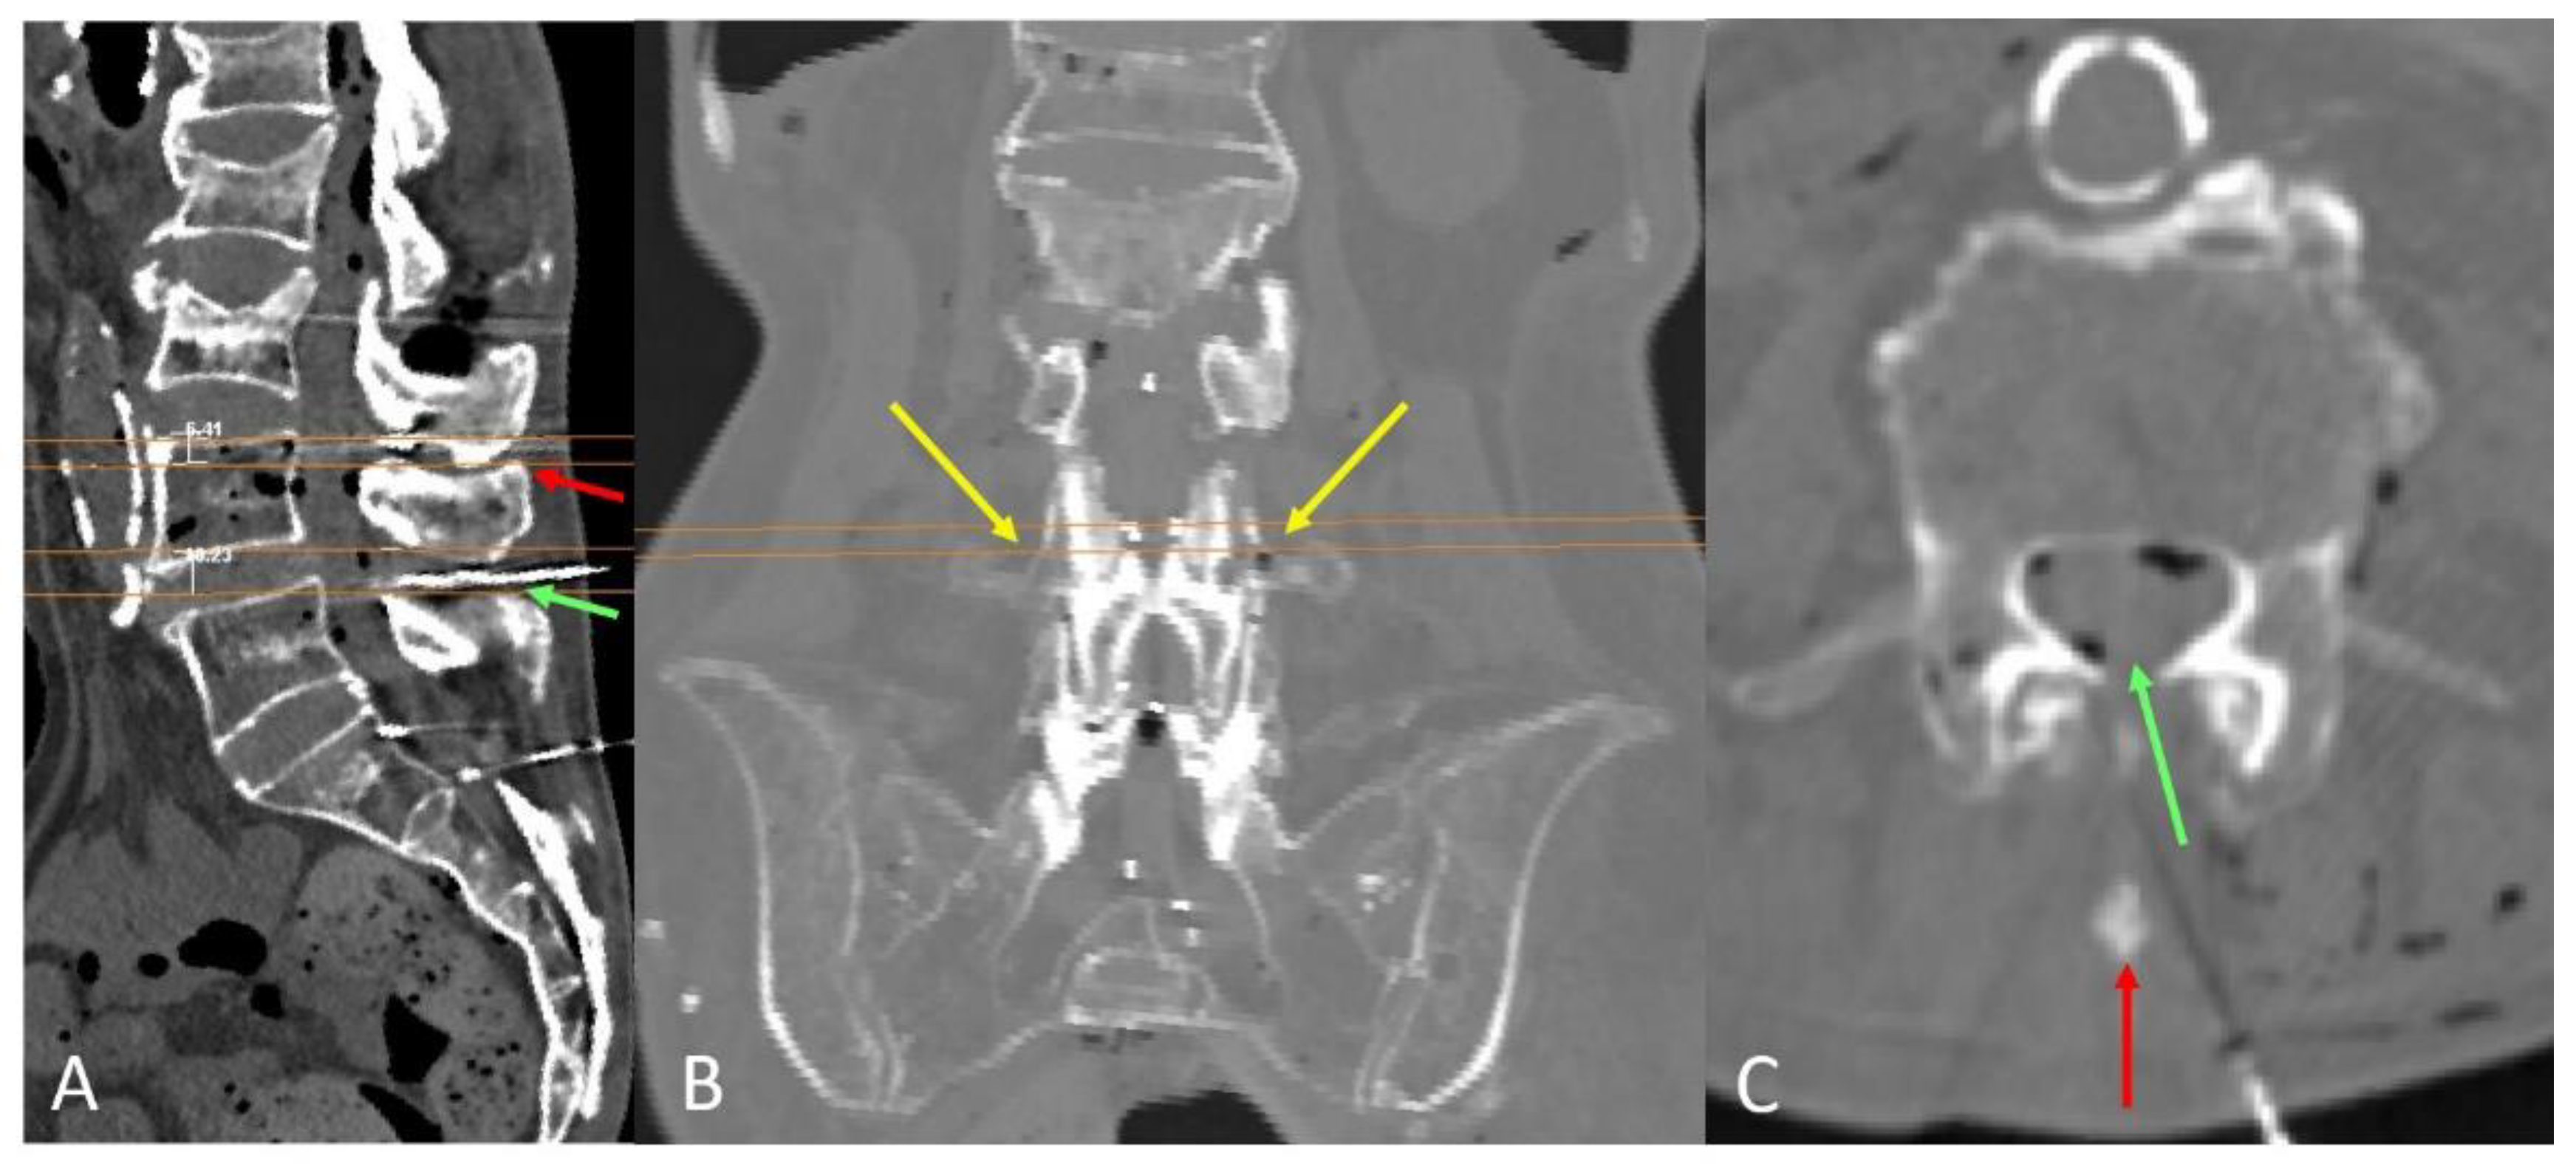

C. Computed tomography of the specimen. Axial and coronal planes are shown. Needles were introduced medially and paramedially at 1 cm on the right side, and at individualized paramedian distances on the left side. The red arrow indicates how the left needle reaches the most ventral part of the spinal canal and slightly penetrates the vertebral body. D. 3D reconstruction. E. Prone position model, illustrating successful perpendicular needle insertions.

Figure 4.

A. Representative case in which the L4–L5 level presents a viable median path (green) for needle insertion, while a prominent spinous process obstructs the midline approach at L3–L4 (red arrow). B. Coronal view of the planes at the level of the transverse process, showing the planes (in orange) suitable for a paramedian and perpendicular approach. This view confirms the alignment of those planes with the upper border of the transverse process (yellow arrows). C. The upper border of the transverse process also indicates the level with a wider interlaminar window, where a paramedian approach is feasible (green arrow), even when the spinous process blocks access via the midline (red arrow).